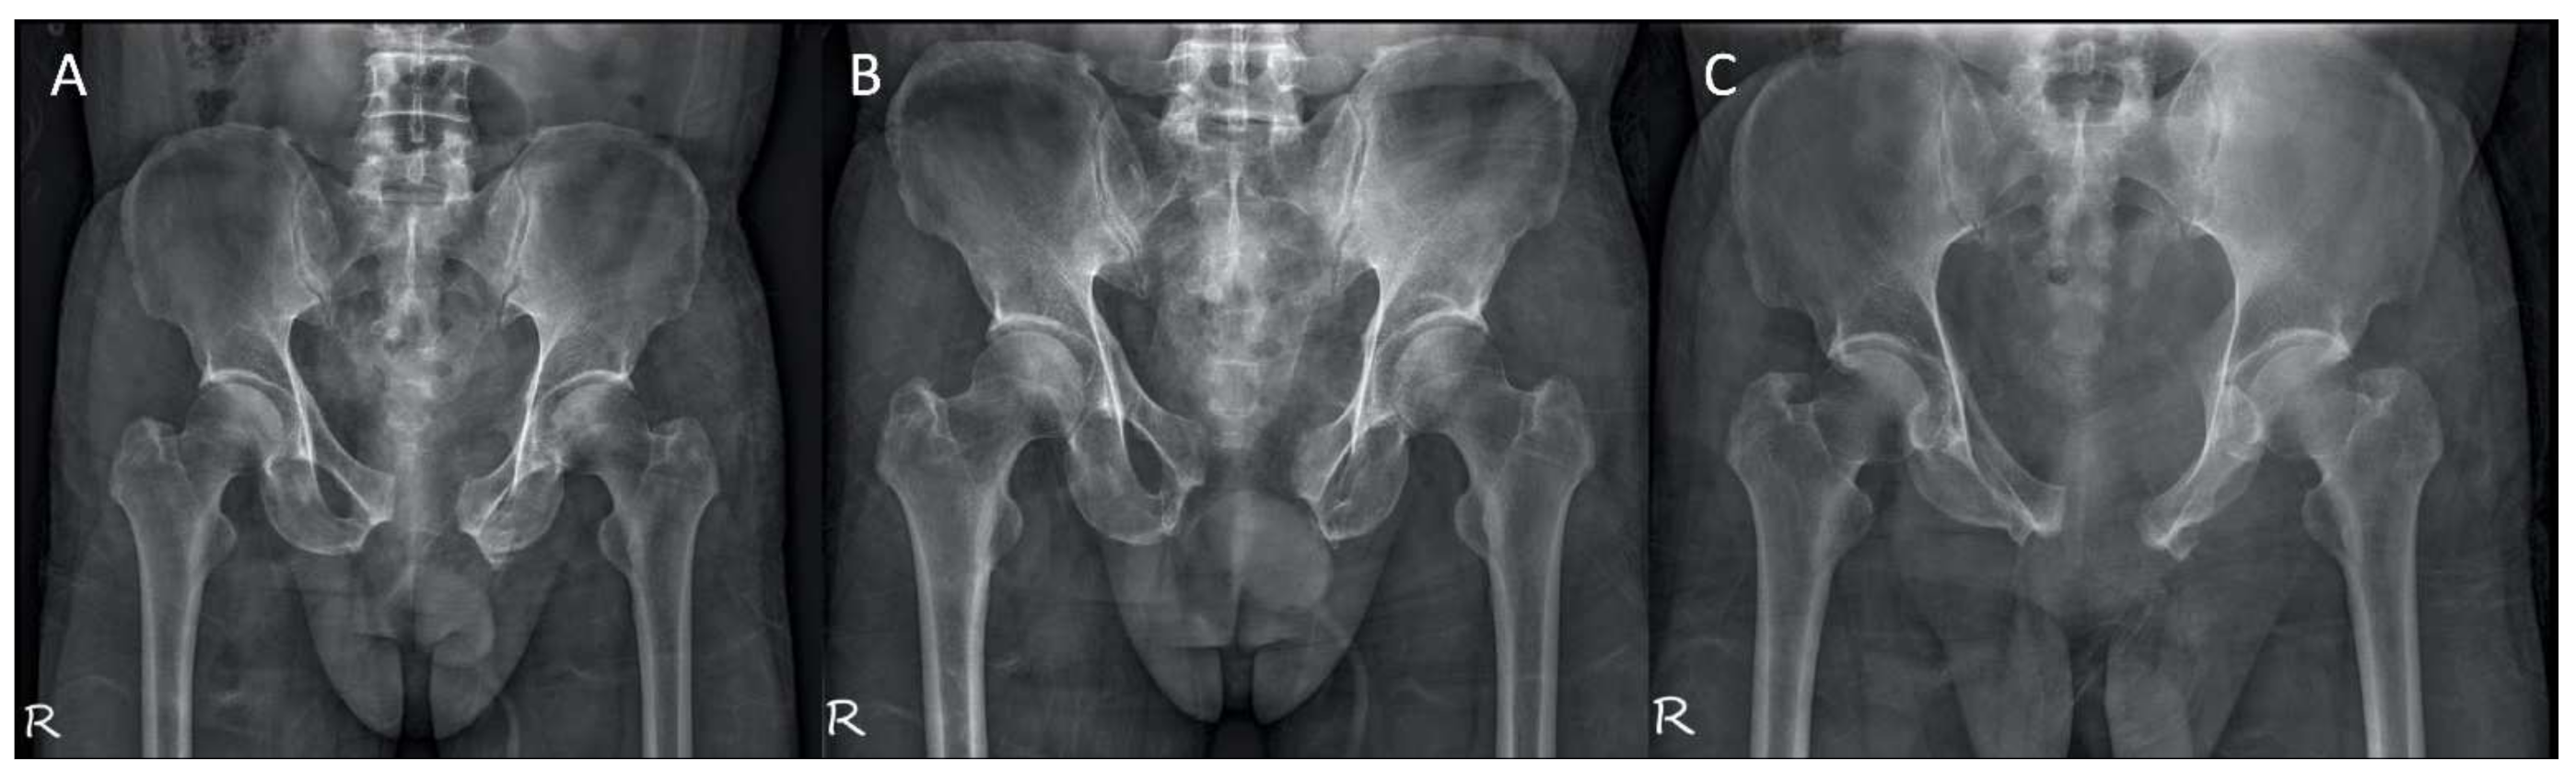

- Hung, C.C.; Li, Y.T.; Chou, Y.C.; Chen, J.E.; Wu, C.C.; Shen, H.C.; Yeh, T.T. Conventional plate fixation method versus pre-operative virtual simulation and three-dimensional printing-assisted contoured plate fixation method in the treatment of anterior pelvic ring fracture. Int. Orthop. 2019, 43, 425–431. [Google Scholar] [CrossRef] [PubMed]

- Hsu, C.L.; Chou, Y.C.; Li, Y.T.; Chen, J.E.; Hung, C.C.; Wu, C.C.; Shen, H.C.; Yeh, T.T. Pre-operative virtual simulation and three-dimensional printing techniques for the surgical management of acetabular fractures. Int. Orthop. 2019, 43, 1969–1976. [Google Scholar] [CrossRef]